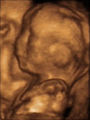

Prenatal development and sonograph images

Prenatal development is divided into two primary biological stages. The first is the embryonic stage, which lasts for about two months. At this point, the fetal stage begins. At the beginning of the foetal stage, the risk of miscarriage decreases sharply, all major structures including hands, feet, head, brain, and other organs are present, and they continue to grow and develop. When the fetal stage commences, a fetus is typically about 30 mm (1.2 inches) in length, and the heart can be seen beating via sonograph; the fetus bends the head, and also makes general movements and startles that involve the whole body. Brain stem activity has been detected as early as 54 days after conception, and the first measurable signs of EEG activity occur in the 12th week. Some fingerprint formation occurs from the beginning of the fetal stage.

One way to observe prenatal development is via ultrasound images. Modern 3D ultrasound images provide greater detail for prenatal diagnosis than the older 2D ultrasound technology. Whilst 3D is popular with parents desiring a prenatal photograph as a keepsake, both 2D and 3D are discouraged by the FDA for non-medical use, but there are no definitive studies linking ultrasound to any adverse medical effects. The following 3D ultrasound images were taken at different stages of pregnancy: